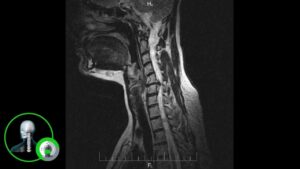

МРТ (магнитно-резонансная томография) шейного отдела позвоночника — это неврологическое исследование, которое позволяет получить детальные изображения структур шейного позвоночника. Этот процесс особенно важен для диагностики, предотвращения и лечения различных заболеваний и состояний позвоночника. В этой статье мы рассмотрим причины, почему стоит делать МРТ шейного отдела позвоночника.

1. Диагностика и выявление проблем: МРТ шейного отдела позвоночника является надежным методом диагностики и позволяет выявить различные проблемы и состояния, связанные с позвоночником. Это может включать грыжи дисков, остеохондроз, воспалительные процессы, опухоли и другие патологии. МРТ позволяет получить детальные изображения, которые помогают врачам точно определить причину симптомов и назначить соответствующее лечение.

3. Планирование хирургического вмешательства: МРТ шейного отдела позвоночника играет важную роль в планировании хирургического вмешательства при необходимости. Он предоставляет детальные изображения позвоночника, которые помогают хирургам определить точное местоположение и характер проблемы. Это позволяет разработать более точные планы операции и минимизировать риски для пациента.